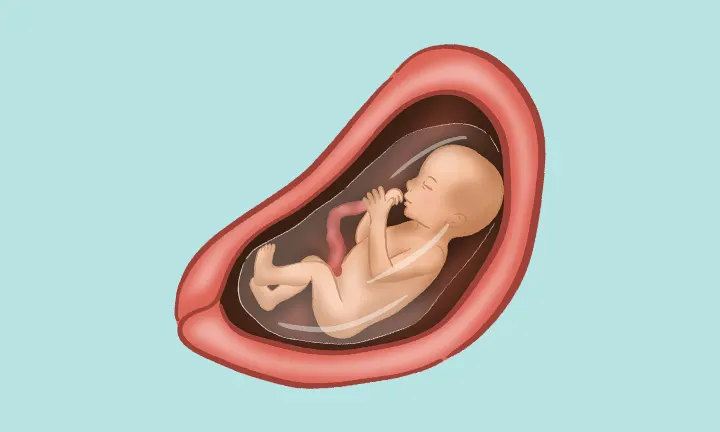

Ҳафтаи 21-уми ҳомиладорӣ яке аз марҳилаҳои ҷолиб ва пурэнергияи давраи модаршавӣ ба ҳисоб меравад. Дар ин вақт ҷанини шумо тақрибан 18–25 сантиметр қад ва тақрибан 390–400 грамм вазн дорад — ба андозаи як банани калон. Ӯ дар дохили моеъи амниотикӣ озодона ҳаракат мекунад, дасту по меандозад ва фазои кофӣ дорад, то ки чарх занад, тебпалезад ва бо қувваи бештар ҷунбад.

Ин ҳафта давраи муҳим барои рушди системаи асаб мебошад: мағзи ҷанин бо суръати баланд инкишоф меёбад, пайвастҳои нави асабӣ пайдо мешаванд ва ҳамоҳангии мушакҳои ӯ беҳтар мегардад. Аз ҳамин сабаб теппазаниҳо ва ҳаракатҳои ҷанин равшантар ва мунтазамтар эҳсос мешаванд. Бисёр модарон дар ин марҳила аввалин бор имконият меёбанд, ки ҷунбиши ҳақиқии ҷанинро эҳсос кунанд ва ҳатто падар метавонад ҳаракатро аз берун ҳис кунад.

Ин марҳила оғози нисфи дуюми ҳомиладорӣ аст — даврае ки ҳам шумо ва ҳам ҷанин ба рушди устувор ва калоншавии босуръат ворид мешавед.

Дар ин ҳафта ҷанин ба нисфи вазни таваллуд мерасад. Ӯ давра ба давра бедор ва хоб мешавад ва ин сабаб мешавад, ки шумо дар як соат чанд маротиба теппазанӣ ҳис кунед.

Ҷанин ҳоло бештар ба кӯдаки навзод монанд мешавад: